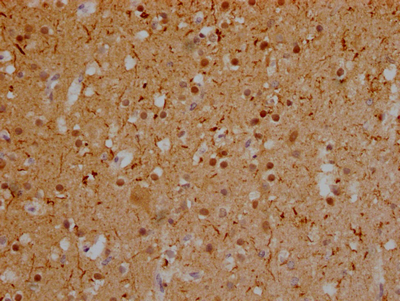

IHC image of CSB-RA246354A0HU diluted at 1:100 and staining in paraffin-embedded human glioma cancer performed on a Leica BondTM system. After dewaxing and hydration, antigen retrieval was mediated by high pressure in a citrate buffer (pH 6.0). Section was blocked with 10% normal goat serum 30min at RT. Then primary antibody (1% BSA) was incubated at 4℃ overnight. The primary is detected by a Goat anti-rabbit IgG polymer labeled by HRP and visualized using 0.05% DAB.

IHC image of CSB-RA246354A0HU diluted at 1:100 and staining in paraffin-embedded human brain tissue performed on a Leica BondTM system. After dewaxing and hydration, antigen retrieval was mediated by high pressure in a citrate buffer (pH 6.0). Section was blocked with 10% normal goat serum 30min at RT. Then primary antibody (1% BSA) was incubated at 4℃ overnight. The primary is detected by a Goat anti-rabbit IgG polymer labeled by HRP and visualized using 0.05% DAB.

產(chǎn)品描述:CSB-RA246354A0HU MAPT重組單克隆抗體是一種高特異性科研試劑,靶向微管相關(guān)蛋白tau(MAPT)。該蛋白廣泛分布于神經(jīng)元中,參與微管組裝與穩(wěn)定,其異常磷酸化及聚集與阿爾茨海默病、額顳葉癡呆等神經(jīng)退行性疾病病理進(jìn)程密切相關(guān)。本抗體經(jīng)ELISA和免疫組化(IHC)嚴(yán)格驗(yàn)證,在IHC應(yīng)用中推薦使用1:50-1:200稀釋度,可清晰檢測石蠟包埋組織切片中tau蛋白的定位與表達(dá)水平,呈現(xiàn)高信噪比的特異性染色效果。適用于神經(jīng)病理學(xué)研究領(lǐng)域,包括tau蛋白異常修飾機(jī)制解析、神經(jīng)退行性疾病動物模型的組織學(xué)分析,以及體外細(xì)胞模型中微管穩(wěn)定性調(diào)控研究。該產(chǎn)品為科研人員提供可靠工具,支持神經(jīng)細(xì)胞生物學(xué)、疾病分子機(jī)制探索及藥物靶點(diǎn)驗(yàn)證等基礎(chǔ)研究,不適用于臨床相關(guān)用途。